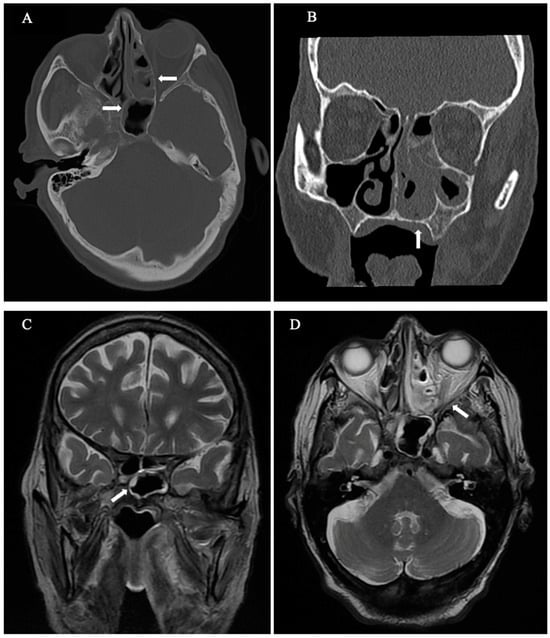

2. Case Description